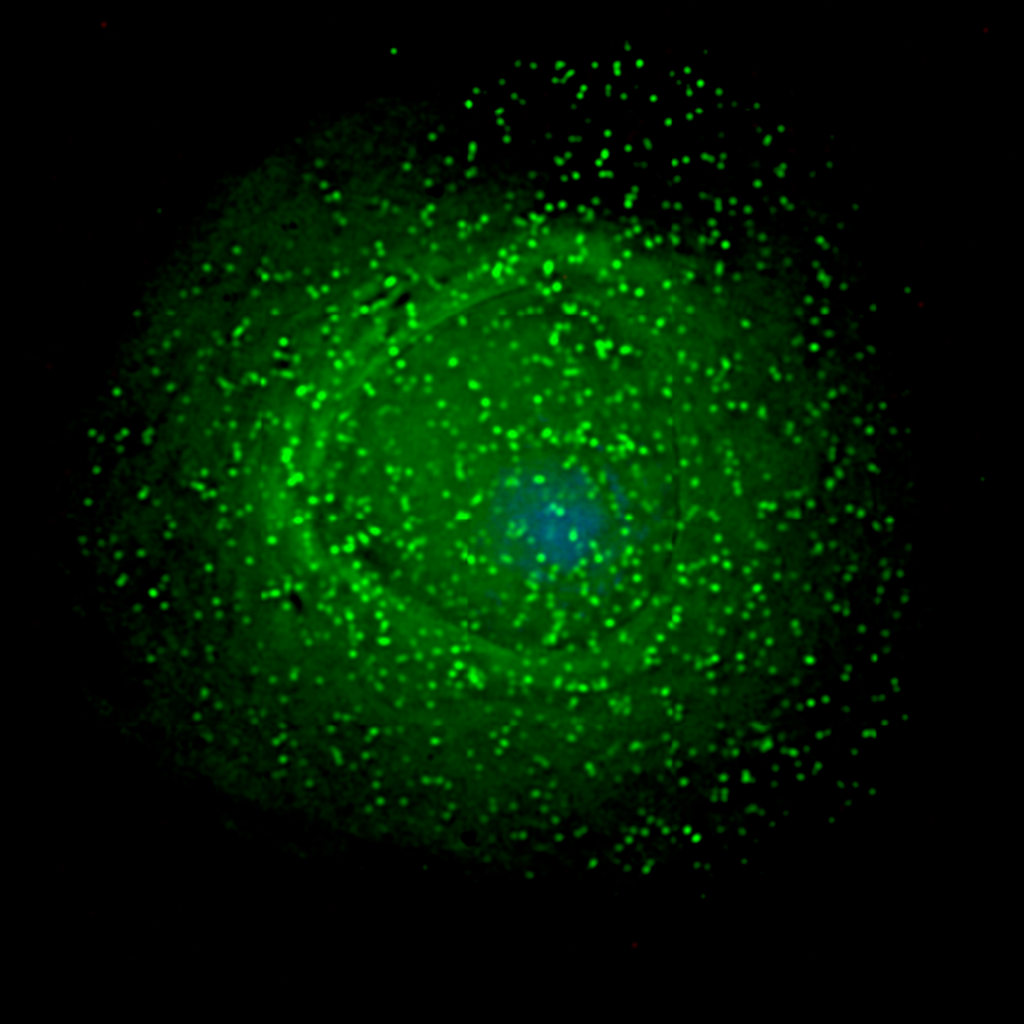

ВИЧ (зеленые точки; розовое — это лимфоцит) на зараженной клетке. Микрофотография: C. Goldsmith Content Providers: CDC/ C. Goldsmith, P. Feorino, E. L. Palmer, W. R. McManus / CDC